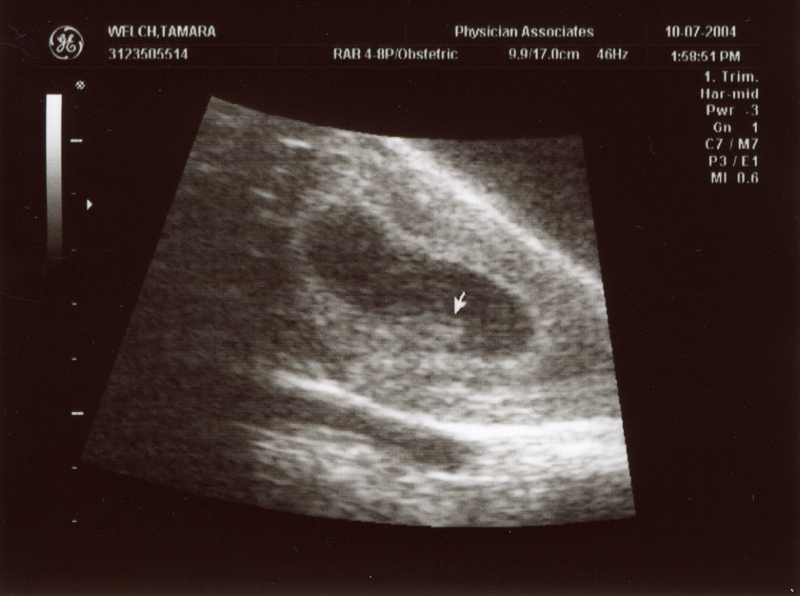

December 21, 2004 - We

had our second ultrasound and found out the sex of the baby. It's

a GIRL! We could see her moving around and see the heart beating.

We also heard the heartbeat during the doctor's visit. The heartbeat

is 150 bpm and the weight is 9 oz. Click on the images below to

see the pictures from the ultrasound. In the image titled "It's

a Girl" you can tell it's a girl because there is nothing

between the legs (the legs are in a "V" shape). We are

thrilled that everything is going well. We are planning to name

her Megan Storey Welch.